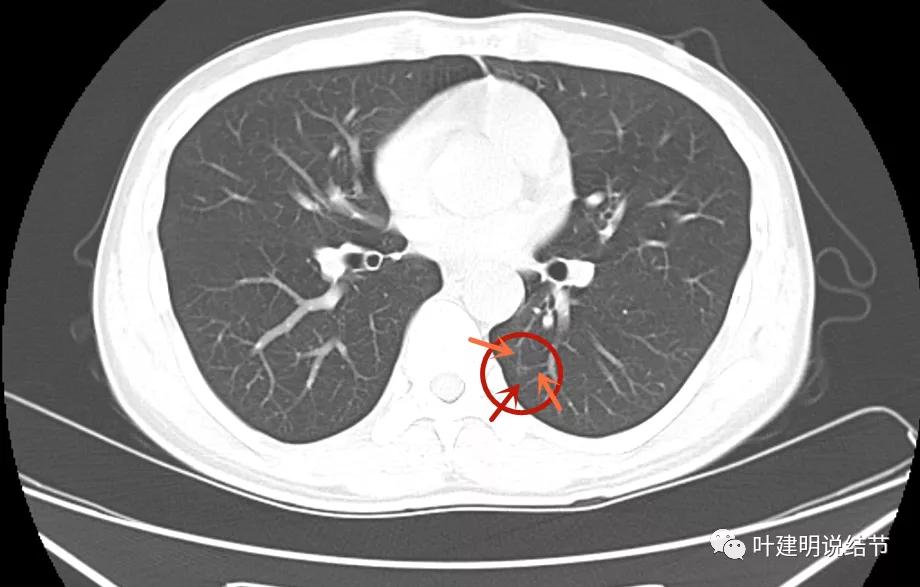

此后不知道为什么试验性抗结核治疗2个月,我感觉结核不太像吧?下面是2022年1月复查的:

病灶1没有明显变化

病灶2也仍在,微血管征仍较明显,病灶本身淡而小

病灶3未见明显显示。

但又有个缺陷,这次又不是薄层扫描。我们能认为病灶3吸收了吗?我觉得是不能够的,刚好没有扫到的可能性大。如果真的是结核,病灶3消失了,病灶1与病灶2也该有所吸收好转呀。所以基本不可能是结核药把病灶3吃好了。

我的意见:病灶1考虑慢性炎伴纤维增生可能性大;病灶2考虑不典型增生可能性大;病灶3可能是肺泡上皮增生或不典型增生,从薄层看也可能是原位。但均可先再随访复查,建议半年后左肺上叶靶扫描加重建以观察主病灶形态仔细。病灶2与病灶3近期没有风险,可年度常规复查。